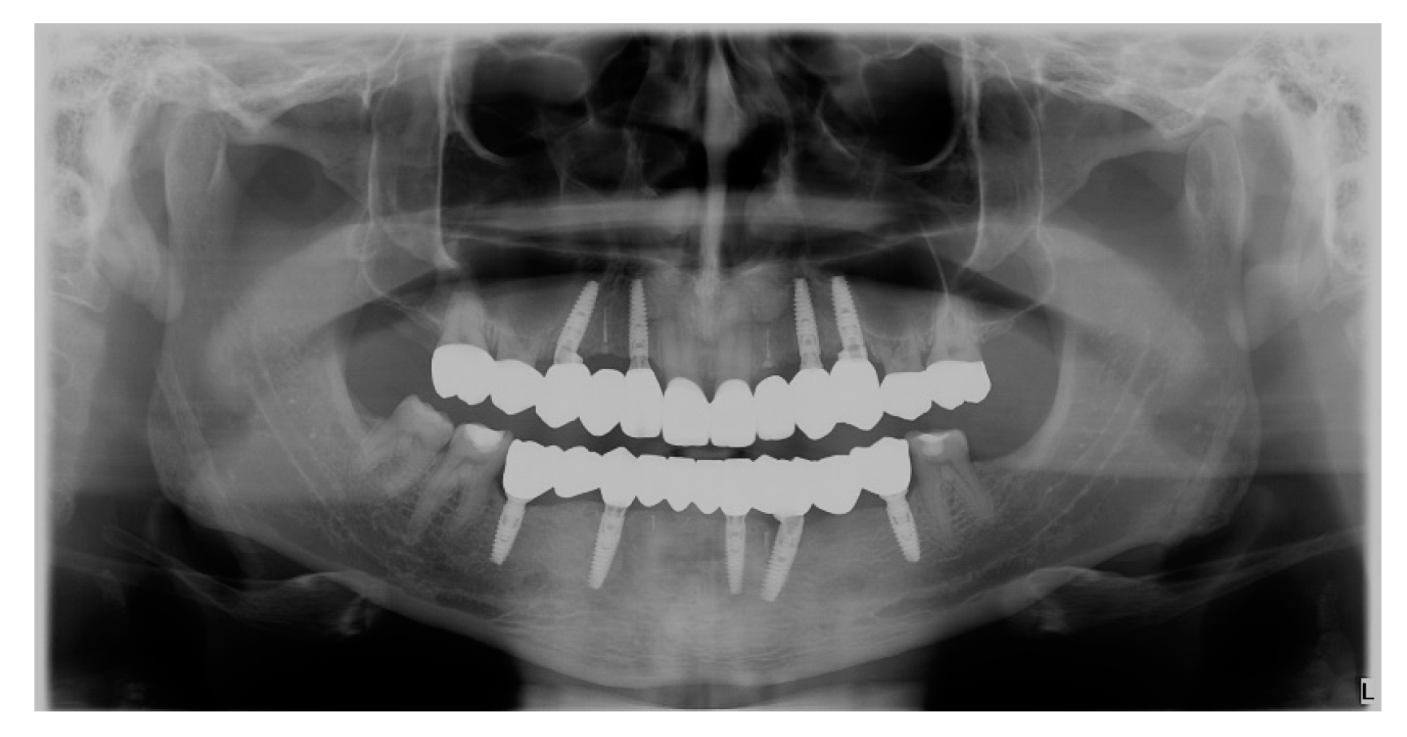

- Upper and lower implant placement with provisional restorations